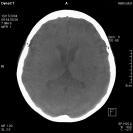

Local bleeding as the result of an aneurysm rupture can now be visualized by syngo DynaCT in the angio lab. In addition, syngo DynaCT allows you to visualize the ventricular system of the brain to aid in diagnosing pathologic processes.

A robotic-based angiography system, syngo DynaCT, offers the interventional radiologist greater flexibility and movement. The system’s flat detector rotates 220 degrees twice around the patient, providing cross-sectional images that can cover up to 47 cm. The liver and lungs can also be covered fully.